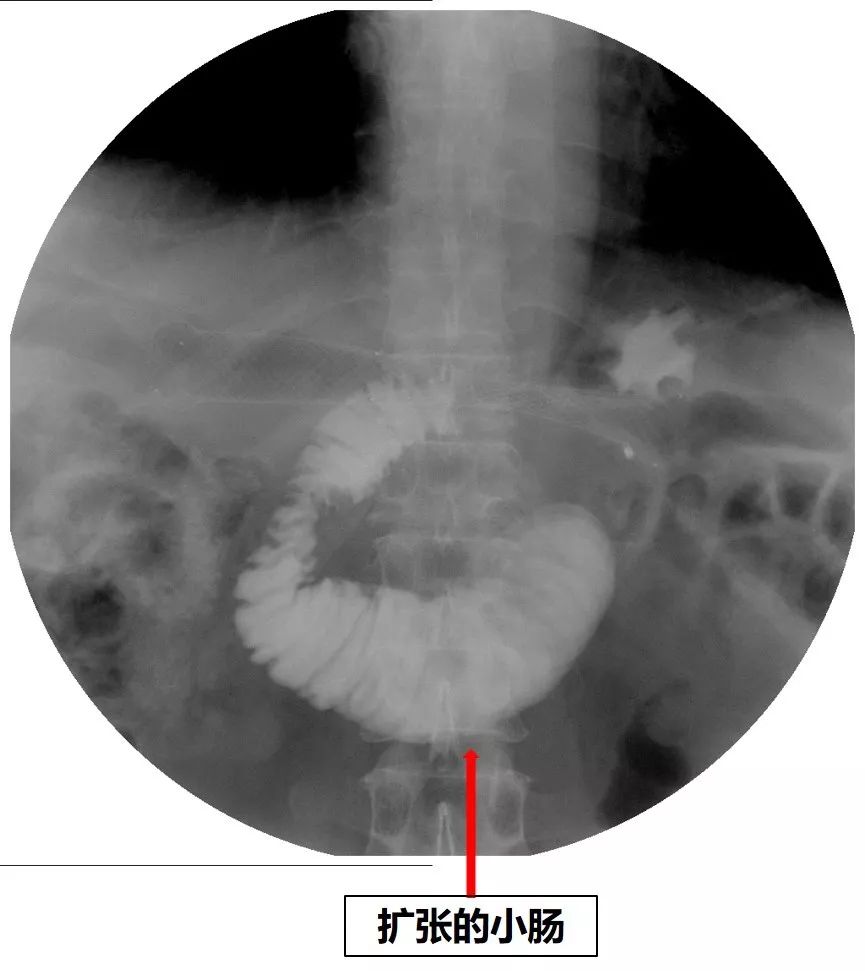

2018年8月底,患者再次出现恶心、呕吐症状。无明显的腹痛症状,无发热。上消化道碘油造影见近端小肠扩张,造影剂通过受阻(图7、图8)。

图7 上消化道造影见近端小肠局部明显扩张

图8 消化道造影见扩张的小肠段远端有局限的狭窄,造影剂通过不畅